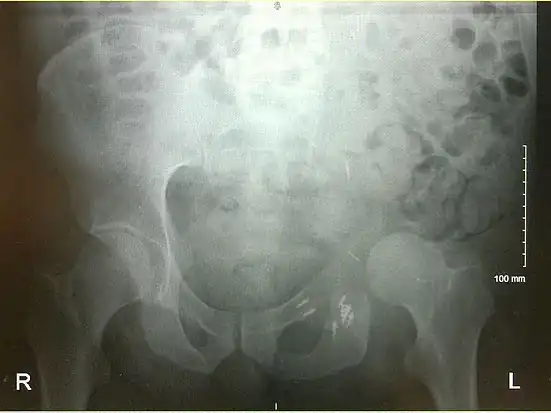

Prior to performing a hemipelvectomy, surgeons must possess detailed knowledge of the pelvic anatomy and its relation to the pelvic tumor.[1] Imaging studies such as conventional radiography, computed tomography, and magnetic resonance imaging help the surgeon visualize the anatomy and its relationship to the local pathology.[1] Surgical oncology techniques are utilized when resecting tumors of the pelvis.[1] Such techniques ensure that adequate resection margins are obtained at the time of surgery to minimize tumor recurrence.[1]